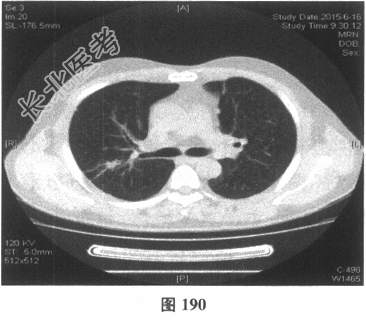

- 多项选择题4.[提示]患者应用多种抗生素治疗(第三代头孢菌素、青霉素加酶抑制剂)包括抗曲霉菌治疗无效,加用甲泼尼龙40mg静脉滴注病情好转。肺部CT检查显示病变明显改善。尿常规检查正常, 肾功能检测正常。复查肺部CT(图188~图195):示病变较前好转。Wegener肉芽肿的主要临床表现是( )